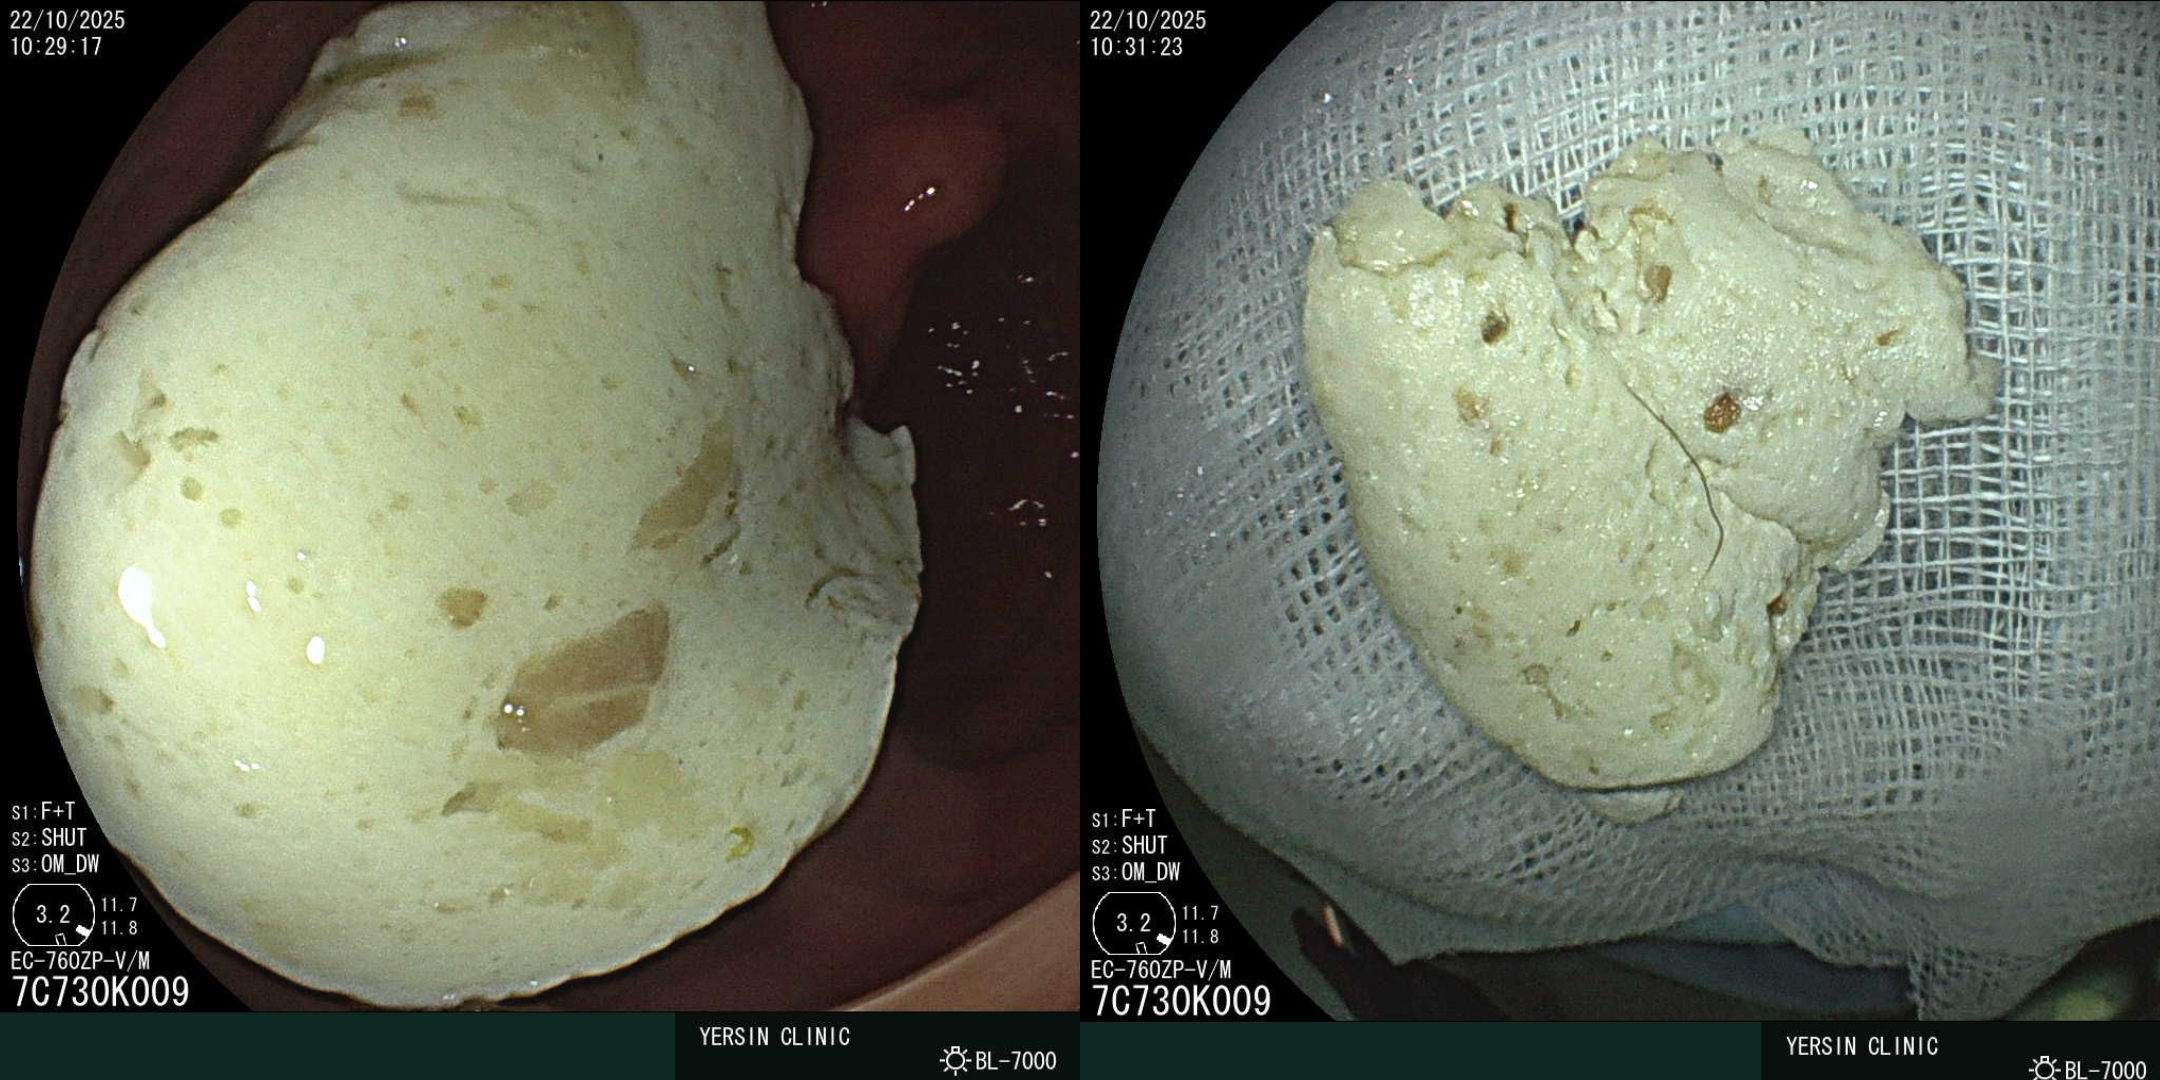

Anh T. được chỉ định nội soi đại tràng. Kết quả mà bác sĩ nội soi quan sát được lại khiến mọi người bất ngờ: tại vùng đại tràng bên trái có một khối dị vật lớn, màu trắng ngà, có độ dai và bám chặt vào thành đại tràng, bơm rửa không trôi. Khối này có đường kính khoảng 5 cm, làm hẹp lòng tương đối.

Dị vật được lấy ra là một khối kẹo cao su cuộn tròn, kích thước ước tính khoảng 5 cm

Sau khi tiến hành gắp dị vật qua nội soi, mọi người kinh ngạc khi dị vật được lấy ra là một khối kẹo cao su cuộn tròn, kích thước ước tính khoảng 5 cm. Ngay sau khi dị vật được loại bỏ, bệnh nhân T. cho biết các triệu chứng chướng bụng và đau bụng đã giảm đi một cách rõ rệt.